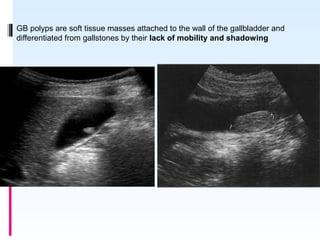

GB POLYPS

 Gallbladder polyps are outgrowths of the gallbladder mucosal wall.

 Do not cast an acoustic shadow.

 Remain fixed on turning the patient ;so distinguishable from stones

 Majority are not neoplastic but are hyperplastic or represent lipid

deposits(cholesterolosis).

 Gallbladder (GB) polyps are incidentally detected in approximately

4%–7% of patients who undergo ultrasonography

GB polyps are soft tissue masses attached to the wall of the gallbladder and

differentiated from gallstones by their lack of mobility and shadowing

On CD demonstration of supplying vessel

pathognomic of polyp.